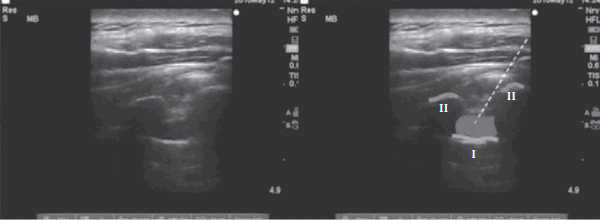

Рис. 3. УЗ-картина при проведении торакальной ПВБ после введения МА

(линия I — париетальная плевра, линии II — очертание поперечного отростка,

серым цветом обозначено введение МА

(Medical Ultrasonography 2010; 12 (3): 223—227)